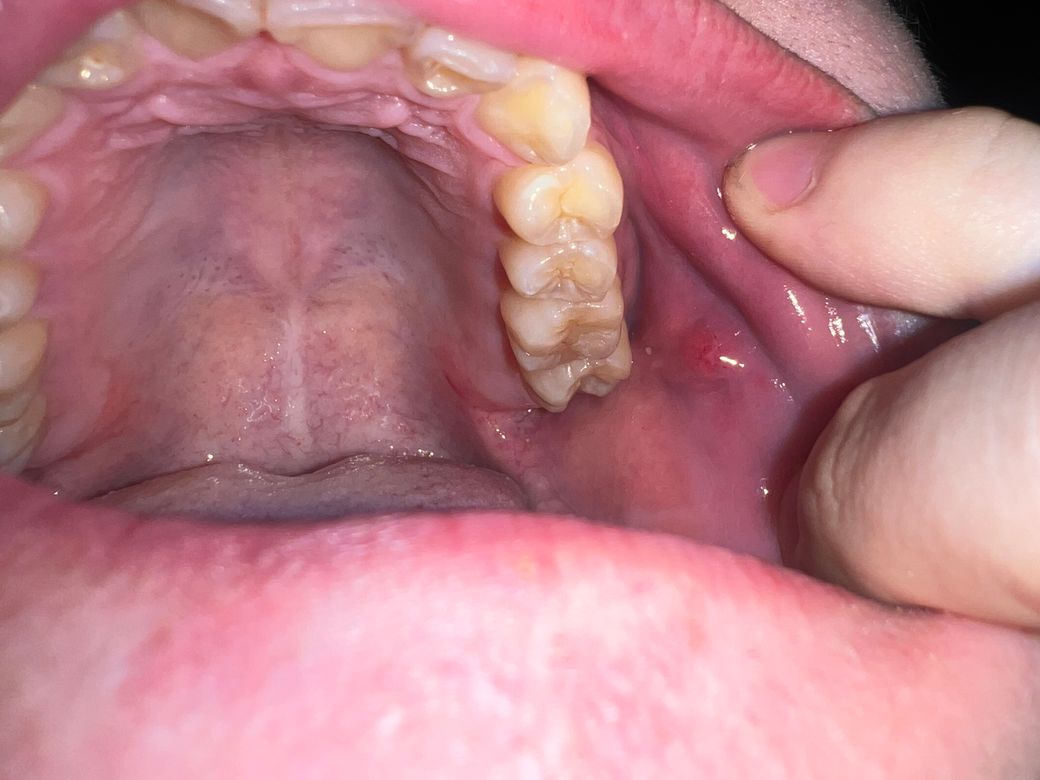

오늘 밥을 먹다가 볼 점막에 혹 처럼 만져지는 게 있어서 사진을 찍었습니다. 사진에서는 잘 안 보이지만 원래 점막을 찢고 나온 거 처럼 아래에 하얀 점막이 보이고 툭 올라온 것에는 붉고 작은 반점이 보입니다 그리고 혀로 건드려도 아프지 않고 딱딱한 게 느껴집니다

Stensen duct로 보여집니다.

걱정은 안하셔도 되겠고 침이 나오는 곳이라고 생각하시면 되겠습니다.

사진상 구내염으로 보이며, 충분한 휴식과 영양섭취를 권합니다. 염증이 덧나지 않도록 소독용 가글인 헥사메딘 가글액으로 가글을 하여 관리하고, 만약 2주이상 사라지지 않는 경우에는 치과 진료를 권합니다.